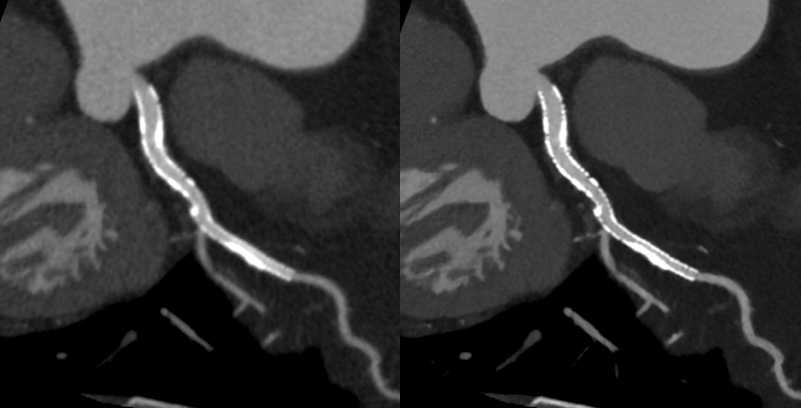

キヤノンメディカルシステムズが開発したPrecise IQ Engine(PIQE)によるディープラーニングの画像によって、冠動脈CT検査で評価が難しい石灰化やステントに接する部分の描出が向上されるため、さらに正確な画像診断が可能となりました。

サブトラクション冠動脈CT

これまで、CTでは評価が難しいとされている冠動脈の強い石灰化部位やステント治療部位において、我々が考案した特殊な撮影(test bolus tracking法)および画像処理技術を用いて評価可能な画像を可能な限り提供しています。

Yamaguchi T. Ichikawa K, Takahashi D. et.al. A New Contrast Enhancement Protocol for Subtraction Coronary Computed Tomography Requiring a Short Breath-Holding Time. Academic Radiology Published online: October 17, 2016